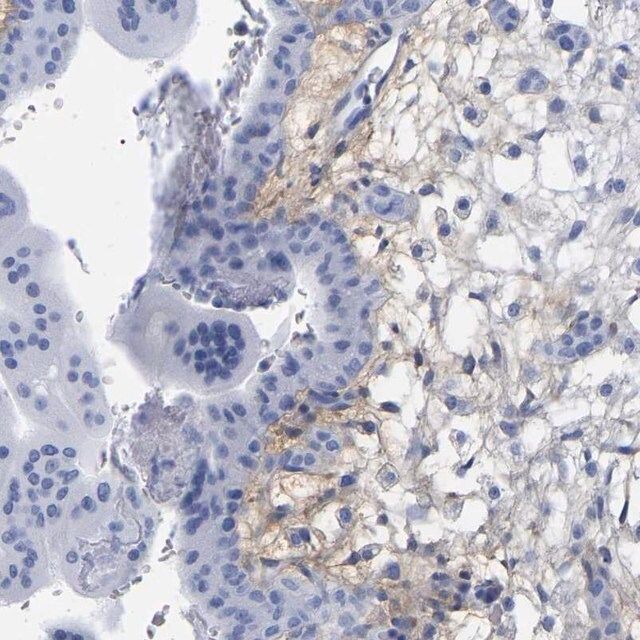

The Human Protein Atlas project can be subdivided into three efforts: Human Tissue Atlas, Cancer Atlas, and Human Cell Atlas. The antibodies that have been generated in support of the Tissue and Cancer Atlas projects have been tested by immunohistochemistry against hundreds of normal and disease tissues and through the recent efforts of the Human Cell Atlas project, many have been characterized by immunofluorescence to map the human proteome not only at the tissue level but now at the subcellular level. These images and the collection of this vast data set can be viewed on the Human Protein Atlas (HPA) site by clicking on the Image Gallery link. To view these protocols and other useful information about Prestige Antibodies and the HPA, visit sigma.com/prestige.

HAPLN1 (hyaluronan and proteoglycan link protein 1) is a crucial component of the cartilage extracellular matrix. It is responsible for connecting proteoglycans to hyaluronic acid, and thereby regulates compression resistance and shock absorption in the joints. HAPLN1 is down-regulated in Kashin-Beck disease and primary osteoarthritis. Single nucleotide polymorphism in HAPLN1 is linked with spinal osteophyte formation and disc degeneration.

- IHC tissue array of 44 normal human tissues and 20 of the most common cancer type tissues.